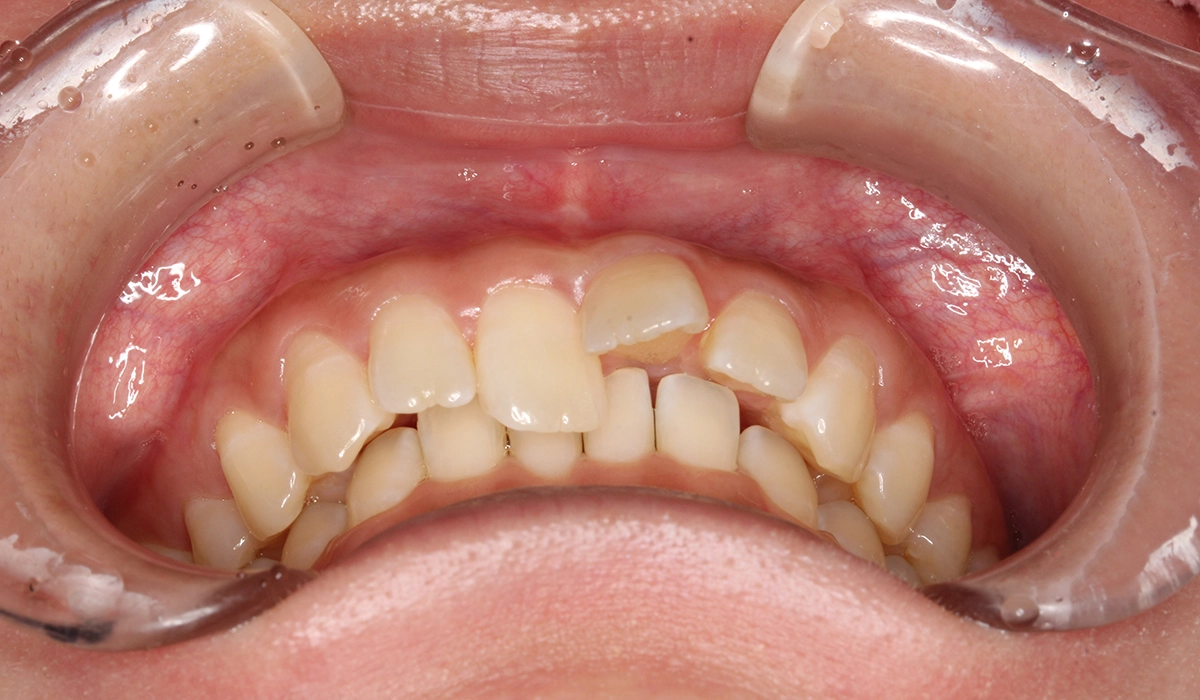

今回ご紹介する患者様は、前歯の噛み合わせの悪さ、歯並び、下の前歯が上の歯茎に当たることを気にされており、矯正検査後叢生Ⅰ級と診断いたしました。

術前:正面

| 主訴 | 前歯の噛み合わせ・歯並びが気になる |

| 治療期間 | 4カ月 |

| 治療費用 | 935,000円(税込) |

| 治療内容 | 前歯の噛み合わせの悪さ、歯並び、下の前歯が上の歯茎に当たることを気にされており、矯正検査後叢生Ⅰ級と診断いたしました。 |